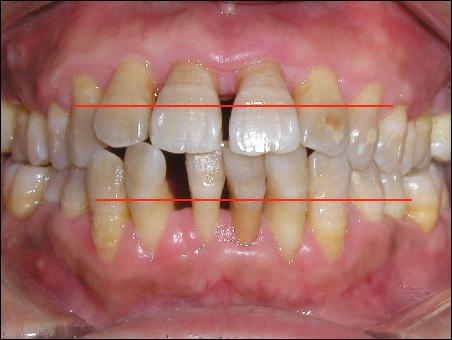

我在微信上發(fā)布了我拔牙的照片后,很多網(wǎng)友產(chǎn)生了疑問,牙齒看起來好好的,為什么要拔牙呢?

通常情況下,蘋果壞掉分為兩種情況,一種是外面,一種是從里面。如果外面的皮破了,然后慢慢爛掉,這種情況就好比齲齒;還有一種情況,蘋果外面看起來好好的,但里邊卻爛掉了,這個就是牙周病。

牙齒附著在牙槽骨上,外面包裹著牙齦。當牙周袋形成后,牙菌斑就會寄居于此,在牙菌斑細菌的作用下就會不斷地發(fā)炎,一方面它會侵蝕牙槽骨,讓牙槽骨慢慢地吸收;另一方面,牙齦腫脹發(fā)炎會降低牙齦與牙齒的附著力,兩種合力共同作用的結果,就是牙齒會越來越松動,直到失去固有的功能。